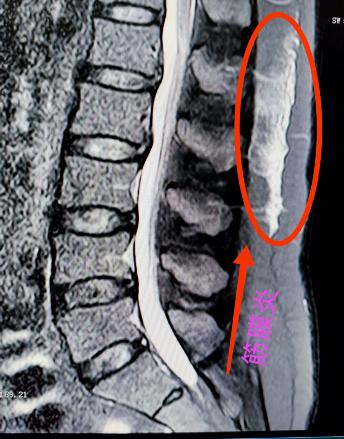

腰椎小关节增生紊乱:腰椎后方两侧成对的小关节,负责稳定脊柱并引导活动。它们如同门上的合页,一旦因劳损、退变导致软骨磨损、骨质增生,或发生微小错位,就会引发深层、定位模糊的腰痛。疼痛常在腰部扭转、后伸时加剧,有时晨起僵硬感明显。